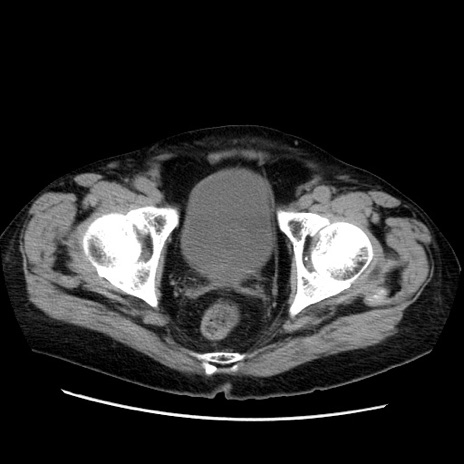

症例21(横断像)

【症例】70歳代男性

【主訴】腹痛

【現病歴】肝硬変・肝細胞癌にてかかりつけの方。約9時間前に食後より腹痛出現。症状が徐々に増悪し、嘔吐出現したため来院。

【既往歴】肝硬変、肝細胞癌(RFA、TACE後)

【身体所見】意識清明、表情苦悶様、BT 36℃、BP 129/78mmHg、P 88bpm、SpO2 97%(RA)、右上腹部から心窩部にかけて圧痛あり、反跳痛なし、筋性防御あり。

【データ】WBC 5800、CRP 0.16